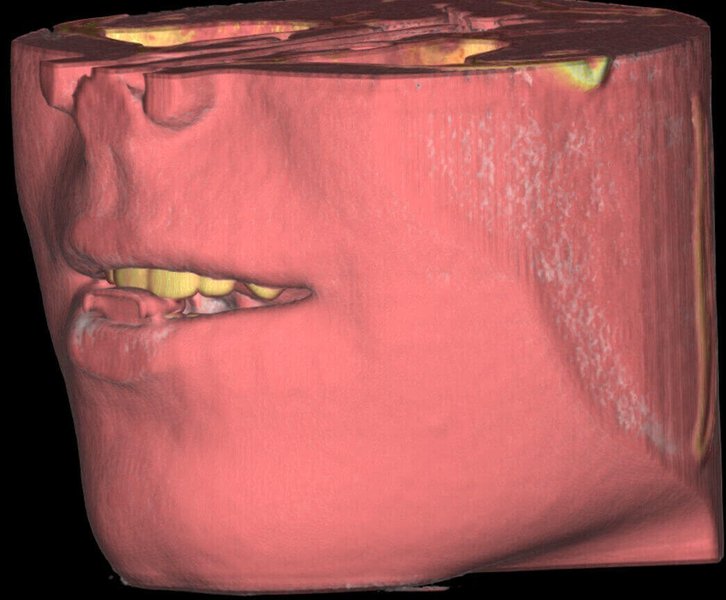

КОМПЛЕКСНЫЙ ГИБРИДНЫЙ КЛКТ ДЛЯ 2D/3D ВИЗУАЛИЗАЦИИ. ИЗОБРАЖЕНИЯ В ВЫСОКОМ РАЗРЕШЕНИИ С ЗАХВАТОМ МЕЛЬЧАЙШИХ ДЕТАЛЕЙ

GIANO HR – универсальное обновляемое устройство от NewTom для всех задач, связанных с радиографией. Благодаря полному диапазону опций 2D и 3D исследования для стоматологии оно предлагает множество особых трехмерных обследований для челюстно-лицевой хирургии, оториноларингологии и осмотра шейного отдела позвоночника. Визуализация только наивысшего качества с технологиями и опытом NewTom

NNT – программное обеспечение NewTom, предоставляющее несколько специальных режимов применения для имплантологии, эндодонтии, пародонтологии, челюстно-лицевой хирургии и радиографии. Это мощное технологически новейшее устройство, разработанное, чтобы снимать и обрабатывать изображения в несколько простых шагов для получения информации, необходимой для конкретного подробного диагноза пациенту. Продвинутое устройство, дающее врачу специальные инструменты для измерения анатомической области (расстояния и углы), нахождения нижнего альвеолярного нерва и замера объема верхних дыхательных путей.